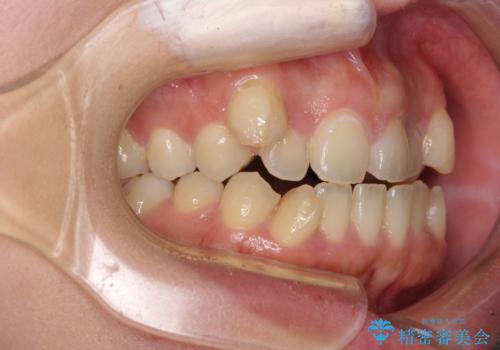

八重歯を抜歯矯正でスッキリと メタルブラケットでの矯正治療

- 八重歯と上下前歯のでこぼこを気にして来院された患者様です。

上下前歯部叢生のスペース獲得のため、上下顎左右小臼歯各1歯(計4本)と全ての親知らずを抜歯して、矯正治療を行うこととしました。